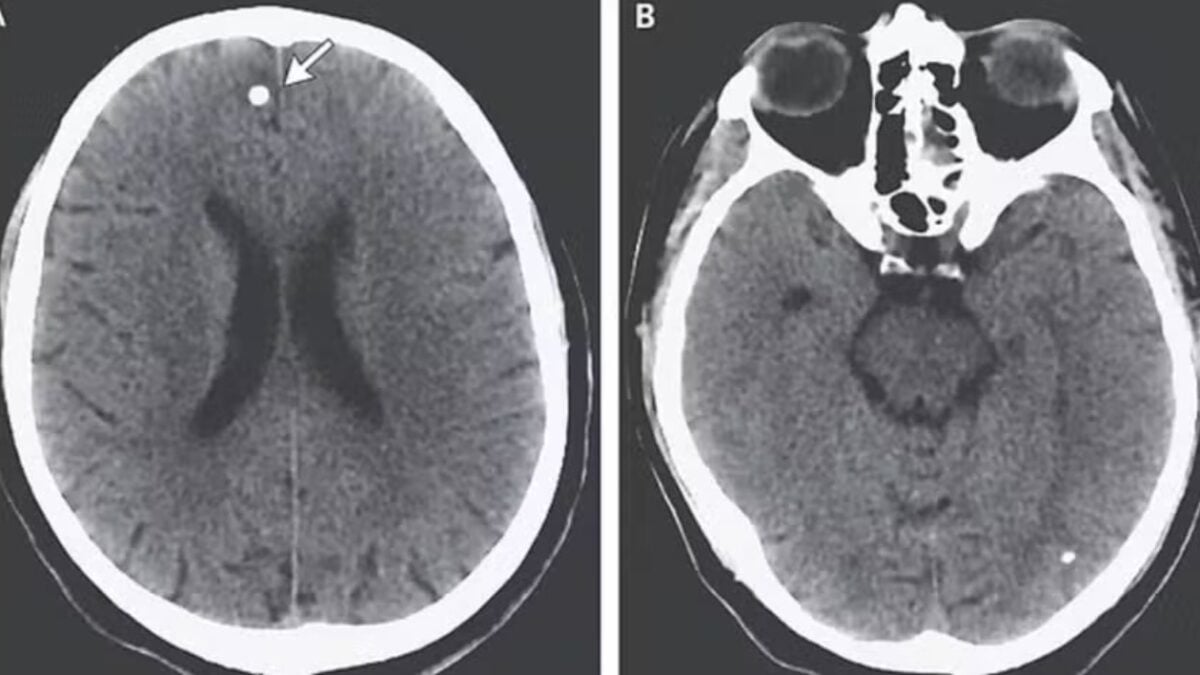

Os médicos, agora examinando seu cérebro mais de perto, encontraram diversas lesões preocupantes no órgão. Após questionamentos persistentes sobre sua dieta e hábitos, “TE” confessou aos médicos que consumia ovos de tênia que havia comprado online. A análise do que exatamente ela havia comprado revelou a presença de tênias pertencentes a duas espécies diferentes de parasitas.

Mas, os problemas no cérebro foram causados pelos ovos da outra espécie, chamada de Taenia solium. Ela é comumente encontrada na carne de porco e libera pequenos ovos que, quando entram na corrente sanguínea, como foi o caso de “TE”, se espalham para tecidos como músculos e cérebro levando a uma doença chamada de cisticercose.

Embora esses ovos não consigam eclodir fora do intestino, eles formam nódulos duros, semelhantes a cistos, que parecem caroços sob a pele. Hsu acrescentou ainda que há casos de alterações na visão, mudanças de personalidade e diminuição da função cognitiva devido a pressão exercida pelos nódulos e pelo inchaço do local, a depender do local em que se alojam no tecido do cérebro.

Quando chega ao cérebro (neurocisticercose), o paciente pode ter dores de cabeça frequentes, convulsões e confusão mental, sendo uma das principais causas de convulsões em adultos na maioria dos países de baixa renda, de acordo com os Centros de Controle e Prevenção de Doenças (CDC) dos Estados Unidos.

Nesse momento, o cérebro ou outro tecido ao redor do cisto pode inchar. A pressão causada pelo inchaço é o que geralmente provoca os sintomas da infecção. Às vezes, os sintomas são causados também pela pressão do cisto em um pequeno espaço, segundo os CDC.